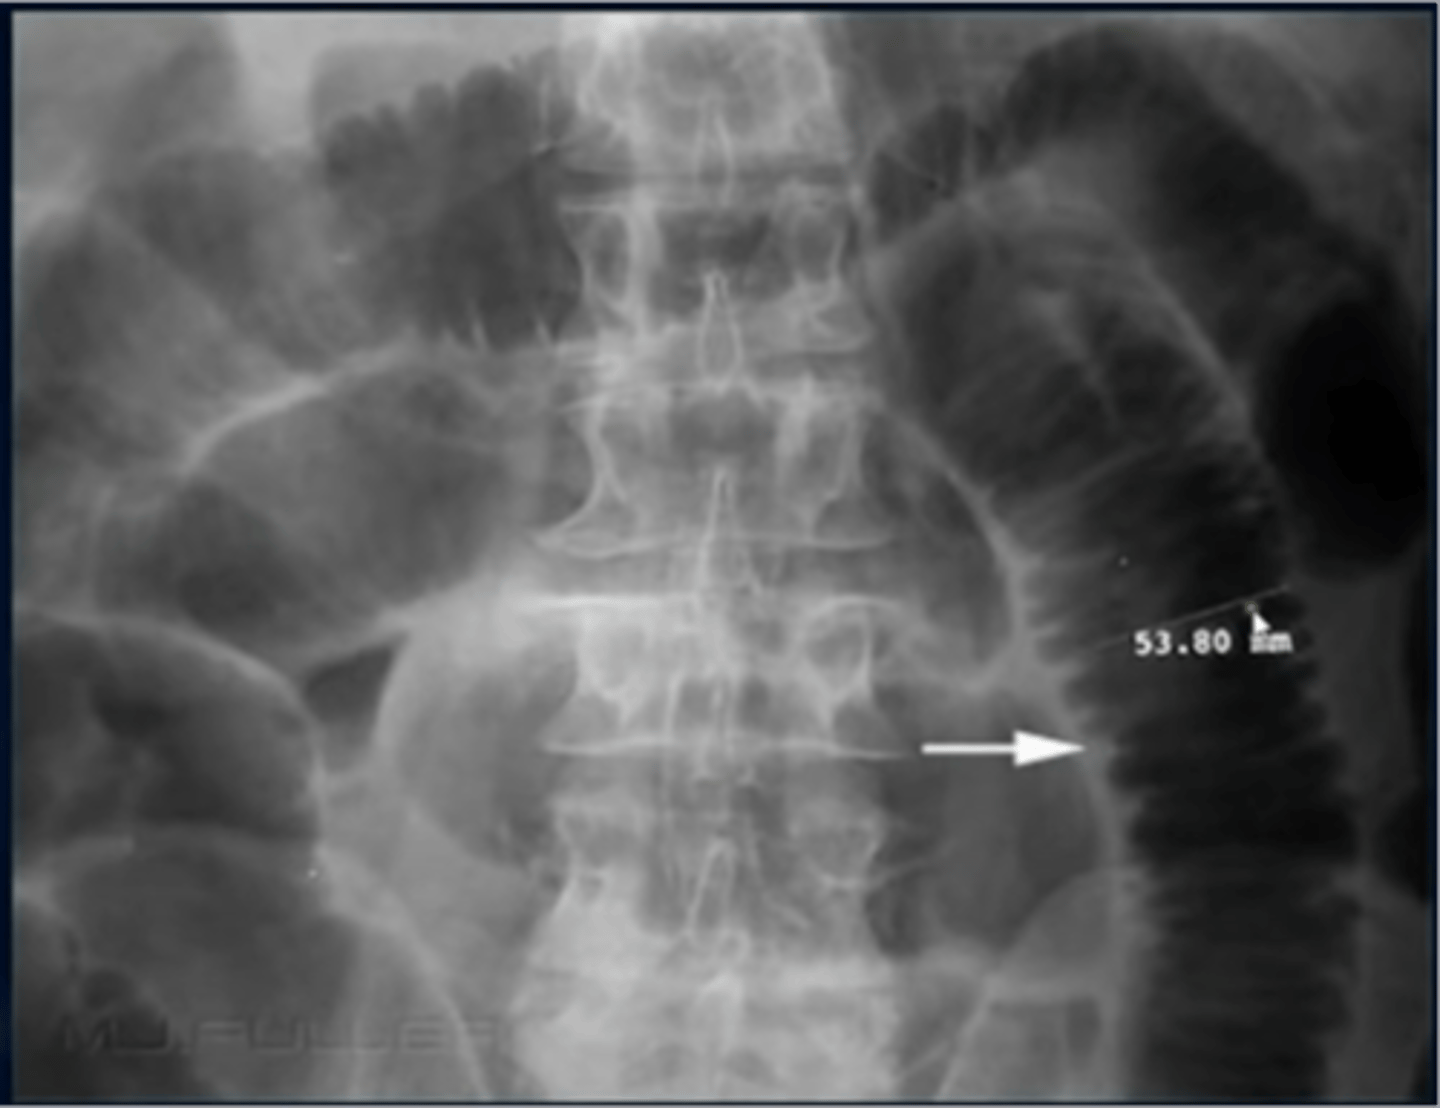

What is an abdominal aortic aneurysm (AAA)?

-enlargement of abdominal aorta

-Risk factors: HTN, atherosclerosis

-usually asymptomatic, but can cause pain

-large ones can rupture lead to hypotension and death

What is a calcified aortic aneurysm?

-common in those with DM and atherosclerosis

-aorta has rim like calcifications

-aneurysm is when normal diameter exceeds 50% of normal size